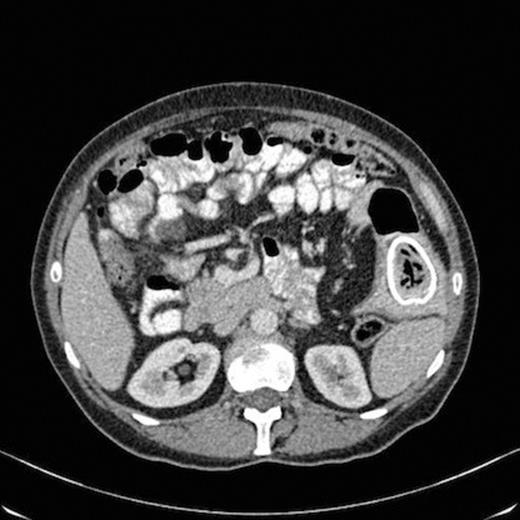

On review by the gynaecologist, clinical examination revealed a normal lower genital tract and cervix with a 12-14cm right adnexial mass and no involvement of the pouch of douglas. A transabdominal and transvaginal ultrasound scan was requested which revealed a 12 cm complex right ovarian cyst with a 3 cm daughter cyst. A CT scan was therefore requested which revealed a large cystic mass within the abdomen and pelvis with solid mural component with invasion of the uterus. There was also finding of an oval calcification in a segment of the small bowel in the left flank situated within a diverticulum with thickening of the small bowel wall at that level (Fig 1).

CT scan showing oval calcification in a segment of the small bowel in the left flank situated within a diverticulum with thickening of the small bowel wall at that level